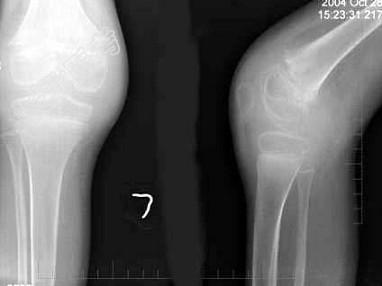

- 单项选择题男,10岁, 左膝关节反复肿胀,伴低热2年, 经抗感染效果不佳,结合图像, 最可能诊断是 ( )

A、左膝关节结核(滑膜型)

B、左膝关节结核(骨型)

C、左膝关节结核(混合型)

D、左膝化脓性关节炎

E、以上均不正确